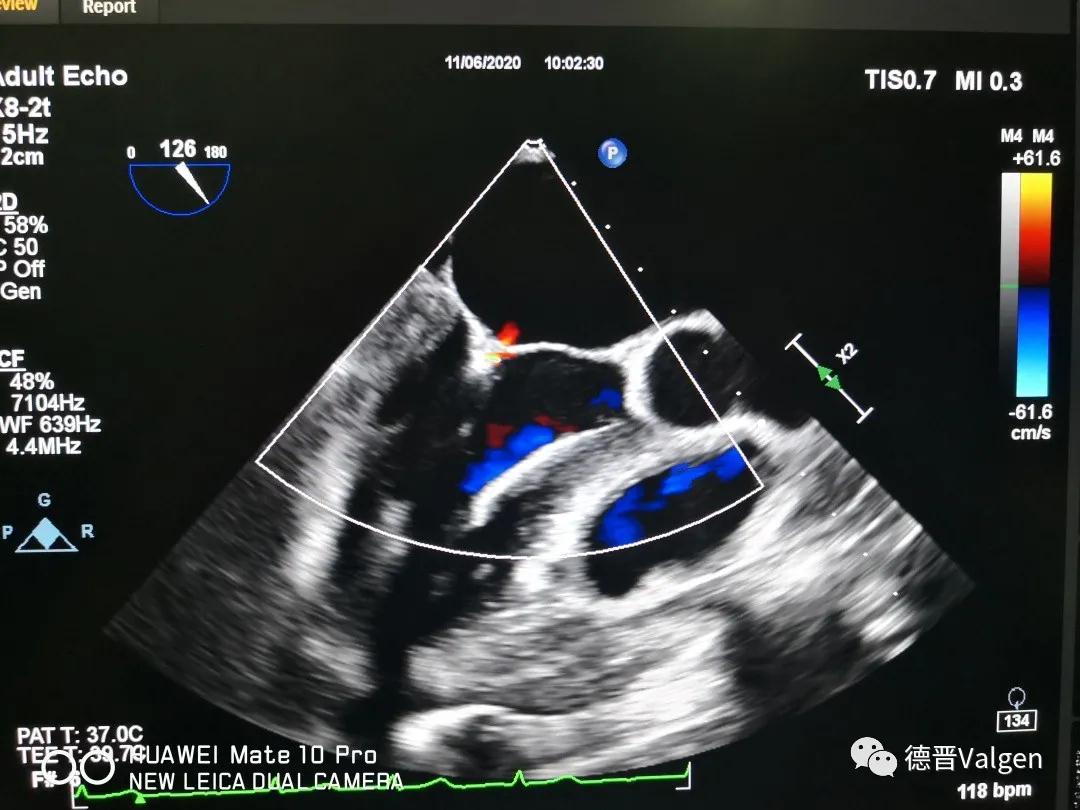

突破!华西医院陈茂教授团队成功开展Dragonfly™手术

德晋医疗专注于结构性心脏病领域尤其是二尖瓣和三尖瓣的相关治疗技术的研发,提供二尖瓣病变系统性解决方案(Tool Box Concept)。德晋医疗曾研发了中国第一款微创介入治疗二尖瓣反流的产品(MitralStitch®),并于2018年1月份成功应用于人体临床。DragonFly™为中国第一款经股静脉二尖瓣缘对缘修复器械,优化的输送系统,使产品可同时应用于三尖瓣介入治疗。德晋医疗成为了国际上唯一具备两种成熟的二尖瓣介入修复器械的公司。德晋医疗的其他二尖瓣和三尖瓣相关器械也在研发当中,公司致力于创新型二尖瓣微创介入治疗全套技术研发,全力推动结构性心脏病治疗领域的发展,让中国智造,惠及世界。